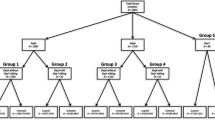

The characteristics of the eight cases are provided in Table 1. Mean female and male age at the time of gamete retrieval was 30.8 ± 3.5 and 32.5 ± 3.3, respectively. Eight different genes were affected, one gene in each case, of which six were of maternal origin. Two semi-informative or informative STR markers were identified and used for each case, except for cases 6 and 8 where three and one STR marker(s) were used, respectively. Mutation detection was used in seven cases, of which two were indirect, using STR markers located within the duplication (case 3) or deletion (case 6). In case 7, direct mutation detection was not possible as the unaffected maternal allele and both paternal alleles had the same number of repeats (non-informative). CVS and blood sampling were performed between gestational weeks 10+5 and 13+0. Figure 1 details the workflow and result from case 1. Detailed figures including STR profiles for the remaining seven cases are available in the supplementary material (Supplementary Figures 1, 2, 3, 4, 5, 6, 7).

Results from case 1. a Flowchart describing the setup and STR markers used for PGT-M and cbNIPT as well as the results and conclusions from PGT, cbNIPT, and CVS. b STR profiles from cbNIPT including paternal and maternal profiles. Insert in the upper right corner details the affected gene and the locations of the STR markers used. Affected alleles are written in red, unaffected in green (the affected parent) or blue (the unaffected parent). Alleles of indeterminable origin are written in black. A couple (29 and 32 years old) seeking PGT due to the female partner being affected by neurofibromatosis type I caused by a deletion (c.7907+4_7del) in the NF1 gene (a). Two STR markers, one fully informative located 1.7 Mb upstream of the NF1 gene (STR 1, NF1-4, see supplementary materials and methods for genomic locations and sequence of self-annotated STR markers) and one semi-informative located 1.3 Mb downstream of the NF1 gene (STR 2, D17S1880), were identified (a insert). Direct mutation detection (by fragment analysis because the mutation is a deletion) coupled with STR analysis was performed on DNA from lysed biopsied trophectoderm cells. An unaffected blastocyst was transferred resulting in pregnancy (a). CVS and blood sampling were performed in gestational week 10+5. Two potential fetal cell samples were isolated from the maternal blood sample (C1-S1 and C1-S2). C1-S2 was classified as inconclusive due to the absence of the paternal allele. C1-S2 was classified as an unaffected fetal cell with the same profile as the transferred embryo. Combined, cbNIPT confirmed the transfer of an unaffected embryo, which was also confirmed by CVS analysis (a). bp, base pair; cbNIPT, cell-based non-invasive prenatal testing; CVS, chorionic villous sampling; Mb, mega bases; PGT, preimplantation genetic testing; PGT-M, PGT for monogenic disorders; STR, short tandem, Cx-Sy, case x sample y